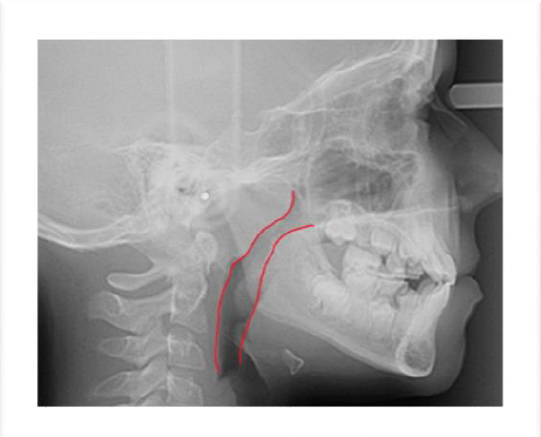

Po lewej stronie zdjęcie, na którym widoczne są zwężone drogi oddechowe przed zabiegiem wycięcia migdałka gardłowego. W rysach twarzy widoczne są cechy wady doprzedniej, min. dolna warga wyprzedza wargę górną.

Po prawej stronie zdjęcie tego samego pacjenta trzy lata po wycięciu migdałka. Drogi oddechowe szerokie, drożne a rysy twarzy i wzajemne ułożenie łuków zębowych poprawiło się i jest w granicach normy.